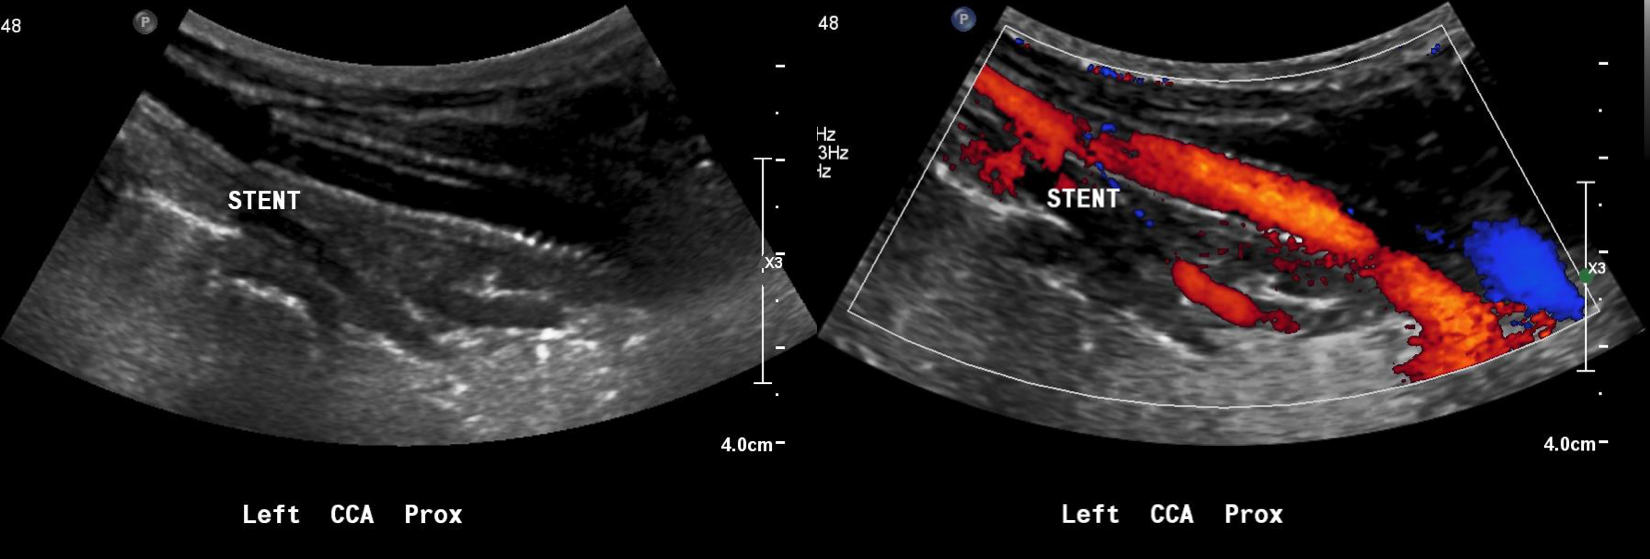

The patient recently returned for a 6 month followup. Duplex showed wide patency of her stent.

7 months post op.png